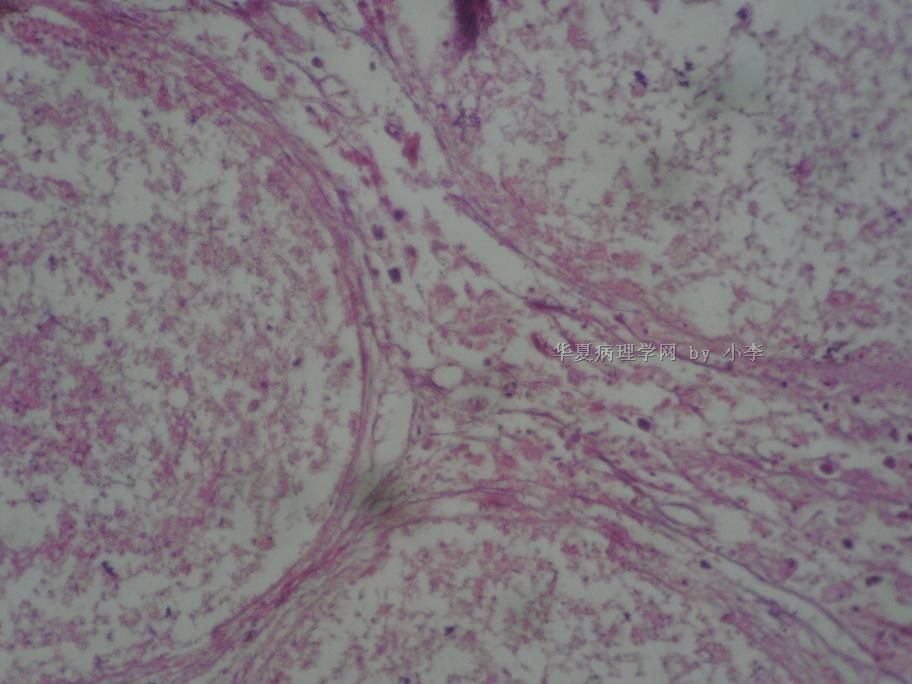

睾丸炎?

• 睾丸炎?图1

图1

首先考虑精子肉芽肿

慢性肉芽肿性炎

肉芽肿性睾丸炎

精子肉芽肿